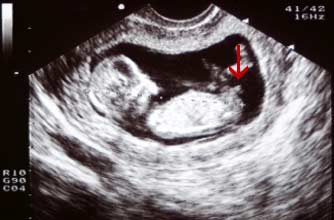

Girl nub: The nub isn't pointing up more than 30 degrees - in fact it's almost horizontal!

小肿块没有指向三十度以上 - 事实上它几乎是水平的!

Boy nub: The nub is at a much steeper angle upwards, indicating that this baby is a boy.

小肿块以一个陡峭的角度向上指,显示这个胎儿是个男孩。